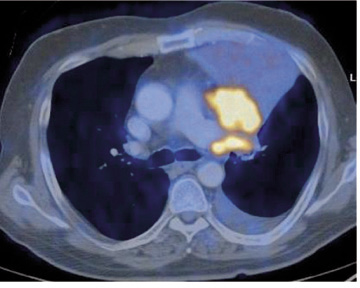

Óbreytt stærð í tvö ár er talið merki um að hnúturinn sé góðkynja (33) og kalkanir benda sömuleiðis frekar til góðkynja hnúta þótt á þessu séu undantekningar. Stakir hnútar geta verið meinvörp frá illkynja æxlum annars staðar (33). Jáeindaskann (JS) (positron emisson tomography, PET) og jáeindasneiðmyndir (JSS)(PET/CT) eru gagnlegar rannsóknir til þess að meta hvort stakur hnútur sé ill- eða góðkynja og er oftast notast við merkiefni sem inniheldur 18F-fluorodeoxyglucose (sjá mynd 6). JS er ekki áreiðanlegt til að meta hnúta undir 1 cm á stærð, en fyrir stærri hnúta er rannsóknin áreiðanleg (34). Nokkuð er um falskt jákvæða hnúta á JS en yfirleitt er talið óhætt að fylgja eftir hnútum sem ekki lýsa upp við þessa rannsókn. Næmi rannsóknarinnar til að greina ?illkynja hnúta er samkvæmt nýlegum rannsókn-um 90-100% og sértækni 69-95% (34).

Mynd 6. Jáeindasneiðmynd af sjúklingi sem var með samfall efst í vinstra lunga á lungnamynd. Skannið sýnir greinilega að orsök samfallsins er æxli miðlægt í efra blaði vinstra lungans.